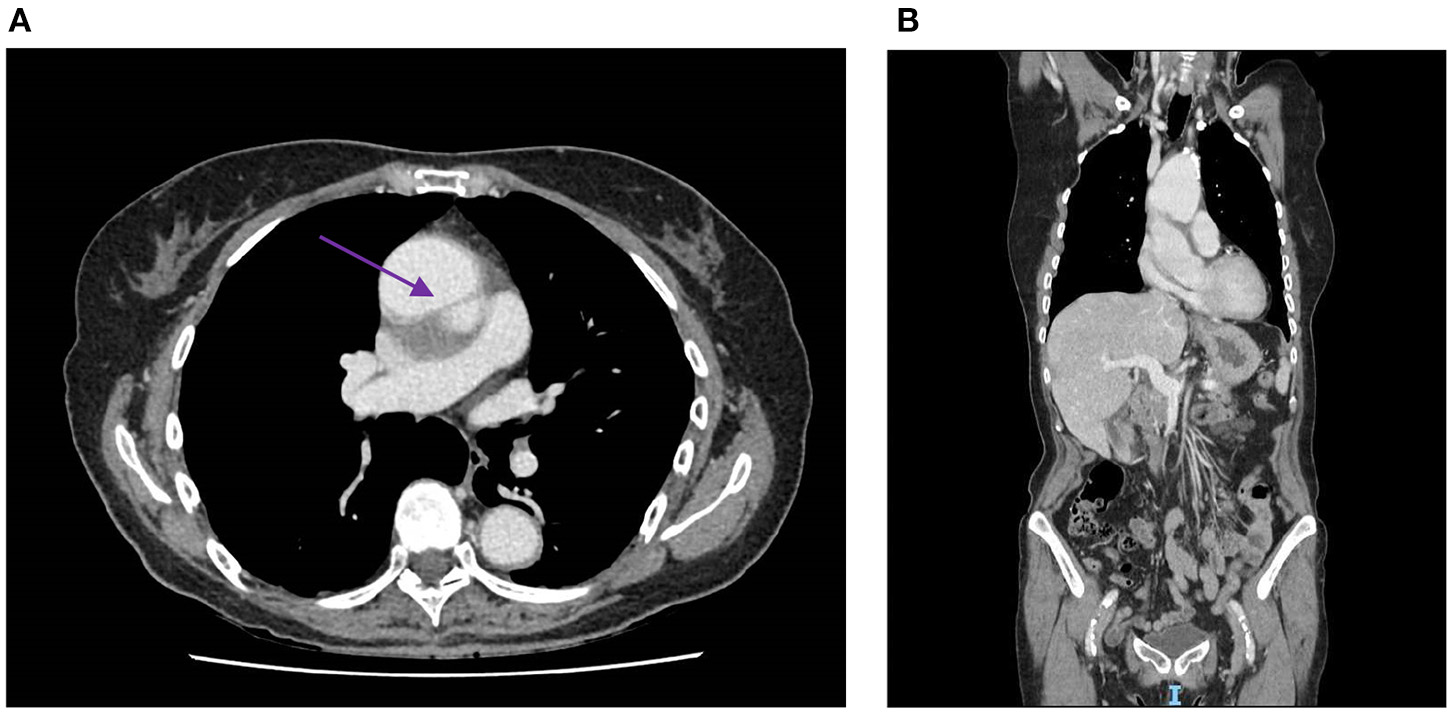

Figure 4

(A) Contrast medium CT scan showing an aneurysm of the ascending aorta (53 × 54 mm) with a tear of the intima, creating a thick false lumen (4 mm), which is indicated by the purple arrow. (B) Sagittal section of the contrast medium CT scan, which also shows the aneurysm and thick tear of the intima. CT, computed tomography.